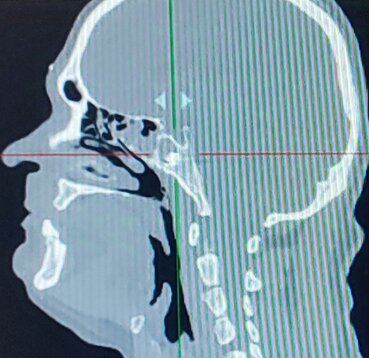

Клинический пример. Раненый П. с огнестрельным слепым ранением средней зоны лица и инородным телом клиновидной пазухи. По результатам КЛКТ головы выявлено инородное тело металлической плотности в левой половине клиновидной пазухи. Под общей анестезией эндоназальным доступом с помощью эндовидеоскопической техники через переднюю стенку выполнено удаление инородного тела. Операция прошла без осложнений.

Компьютерные томограммы раненого в трех проекциях с инородным телом клиновидной пазухи: